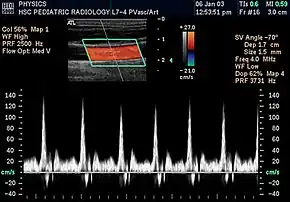

In the 1970s, Strandness and the bio-engineering group at the University of Washington, turned their attention to the use of real-time B-mode scanning. This type of ultrasound would enable physicians to see the vascular structures in real-time. Further research allowed B-mode imaging to be combined with Doppler ultrasound, providing real-time views of the vascular structures and simultaneous hemodynamic information. Today, this type of duplex scanning is used in a variety of ultrasound specialties.[6]

Prior to Strandness' work, the only vascular imaging available to physicians would have been arteriograms, x-rays read from radiopaque dyes injected directly into the bloodstream. Initially, the idea of using ultrasound imaging was met with resistance. Eventually, however, younger physicians were more receptive and accepting of the technology Strandness and his team developed. Although arteriograms are sometimes still used, most physicians today rely upon the non-invasive procedures and real-time information provided by duplex ultrasound scans.[9]

Today, based on the technologies and practices Dr. Strandness developed, vascular ultrasound is a well established field. Technologists, known as vascular sonographers, specialize in this specific branch of ultrasound scanning.[10]